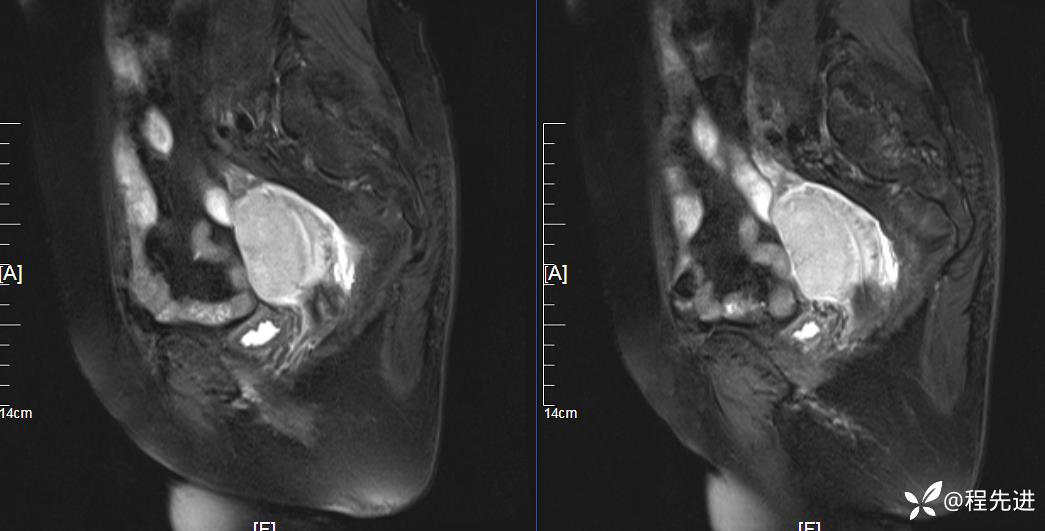

T1: